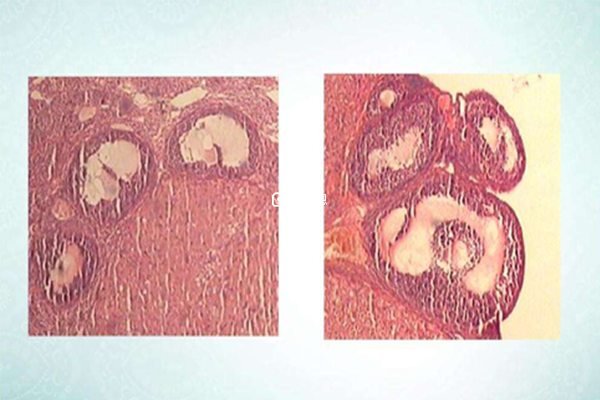

隨著不孕不育人群增多,促排藥物的使用率越來越多,而能夠幫助女性進行促排的藥物非常多,而對於試管拮抗劑促排藥物通常以GnRH拮抗劑為主,而對試管拮抗劑促排藥物來說則是時間以及劑量是非常重要的,而觀察的媒介就是B超。

B超在促排方案中是都不可缺少的,拮抗劑促排方案也並不例外,而其效果就是用來觀察優勢卵泡大小,從而來確定促排針注射的時間以及劑量,但試管拮抗劑促排藥物最多使用在10天。